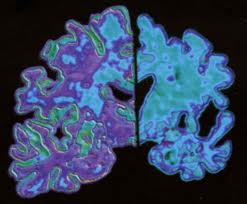

La enfermedad de Alzheimer es la forma más común de demencia. En el parénquima cerebral coexisten ovillos neurofibrilares intraneuronales, depósitos de amiloide extracelulares en forma de placas amiloides, angiopatía amiloide cerebral, y pérdida sináptica y neuronal, siendo las áreas límbicas las más severamente afectadas.

Aunque todavía no se conoce del todo, los resultados clínicos y de la investigación apuntan a una posible relación causal común entre enfermedad de Alzheimer y el glaucoma. Estos dos trastornos neurodegenerativos crónicos comparten biológica y características mecánicas, entre ellas:

lo que sugiere que ambas enfermedades pueden proceder de mecanismos de plegamiento similares. Una presentación de los caminos patogénicos comunes asociados con estos trastornos, incluyendo mecanismos de muerte celular, la producción de especies reactivas de oxígeno, la disfunción mitocondrial y anomalías vasculares, servirán como un punto de inicio para posteriores estudios.